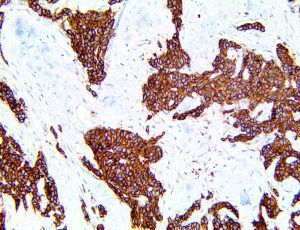

The first cytokines released are interleukin 1β (IL-1β) and tumor necrosis factor-α (TNF-α), which attract a variety of circulating white blood cells (WBCs) to the infection site, including neutrophils, monocytes, macrophages, and natural killer (NK) cells. This response, along with the antipathogenic chemicals released by these cells (i.e., complement), comprise the innate immune response. These cells directly attack the invading pathogen and also release additional cytokines, chief among them interleukin-1 and 6 (IL-6). IL-6 is essential for invoking the adaptive immune response, which calls T-cells, B-cells, and T helper (Th) cells to the infection site. IL-6 also stimulates further recruitment, proliferation and activation of macrophages.

It is the ICU physician who is most likely to witness one of the deadliest manifestations of the abnormal immunological response, the cytokine storm syndrome (CSS). This response is also referred to by some as the cytokine release syndrome (CRS). CSS is characterized by continuous activation and expansion of macrophage and lymphocyte populations, which secrete large amounts of cytokines, causing the cytokine storm. This massive cytokine release is akin to hemophagocytic lymphohistiocytosis (HLH) disease, a syndrome characterized by initial unchecked and persistent activation of cytotoxic T lymphocytes and NK cells.

This activation induces inflammatory monocytes to highly express IL-6, starting a localized and then systemic cascade effect that results in hyperproduction of IL-6, which accelerates the inflammatory process. Because IL-6 also increases vascular permeability, excessive levels cause blood vessels to become very leaky. This, along with clotting factors released from vascular endothelial cells, stimulates the coagulation cascade, resulting in microthrombosis (tiny clots), which leads to ischemia and tissue death of the kidney, intestines, heart, liver, brain and extremities.